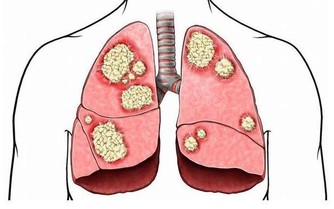

在某些情況下,手臂處的深靜脈血栓會分離出一部分隨血液流動,最終會進入肺部,誘發肺栓塞。

動脈栓塞是指血栓或血管中的異物阻礙了動脈血液流通,當栓塞到達手臂動脈時,